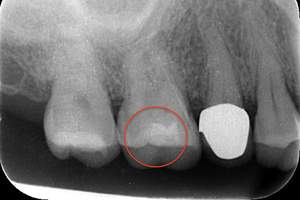

写真のレントゲンを見て頂くとわかると思います。赤丸の歯は、黒い影が歯の真ん中の黒い部分に達していますね。これが虫歯が歯の神経に達しているレントゲン写真になります。このような場合は、虫歯を取り除き歯の神経の治療が必要になり、その後に土台やかぶせ物の治療をします。

レントゲンは、柔らかければ柔らかいほど黒く写り、硬ければ硬い程白く写ります。そのため、虫歯は黒く写ってきます。

虫歯症例のレントゲン写真。虫歯は黒く写ります。